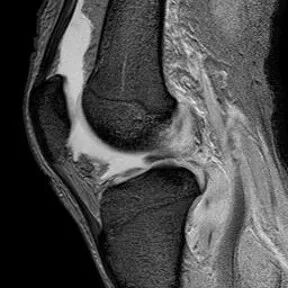

半月板纵行撕裂

1、纵行撕裂2、撕裂方向和半月板长轴方向平行3、垂直或斜行的III级高信号

(半月板纵行撕裂)